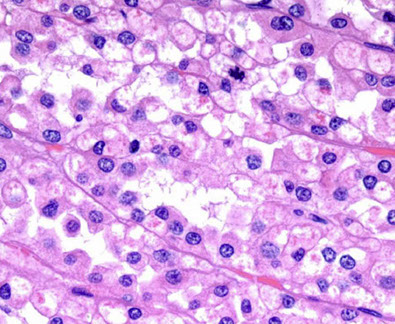

Collapsing Glomerulopathy

Assoc c HIV, blacks, IVDU, but can be 2/2 other causes (pamidronate tx), glomerular loops look like they have been sucked dry, c hypertrophy of glomerular epithelial cells that fill Bowman's space and separate collapsed glomerular tufts

On low power, has some abnormal tubules, which are dilated c casts, c inc cytoplasmic granularity

- glomeruli have collapse of capillary loops c vacuolated granular visceral epithelial cells on outside of collapsed tufts c material similar to tubular casts in Bowman's space

EM: tubulo-reticular bodies (agg of intracytoplasmic tubular structures in the ER)